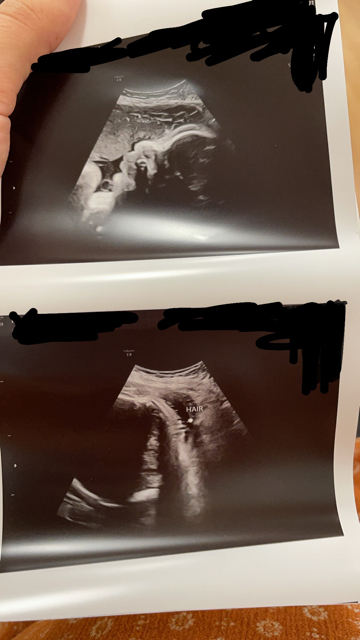

Had my first growth scan!! If I go another week they expect an 8 pounder right now they think he’s 7 pounds but could always be off by a pound measuring one day ahead!!!